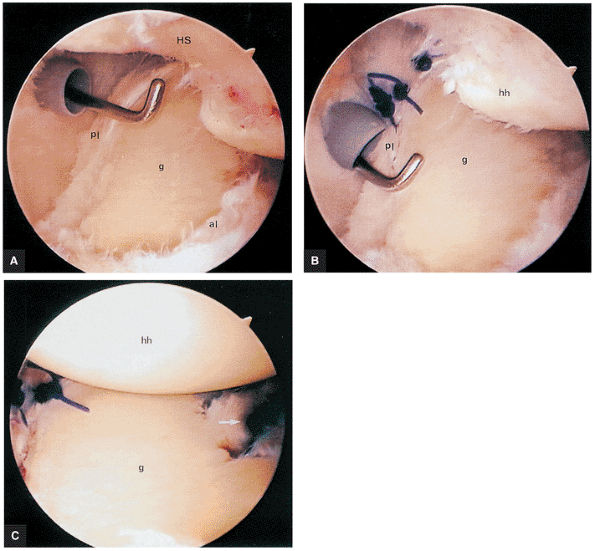

and optimized signal-to-noise or MR arthrograms using the ABER position. MR examinations are important in identifying partial-thickness articular surface tears of the rotator cuff and peel-back lesions. MR examinations in microinstability include:

-

Posterior coronal images and sagittal and axial images display peel-back lesions with posterosuperior labral tears. Axial and sagittal images may further show an early pattern of eccentric sclerosis or wear as a pre-posterior peel-back lesion.

Coronal plane images are used to distinguish a type 2 or 3 BLC with a normal biceps labral sulcus from a SLAP lesion.